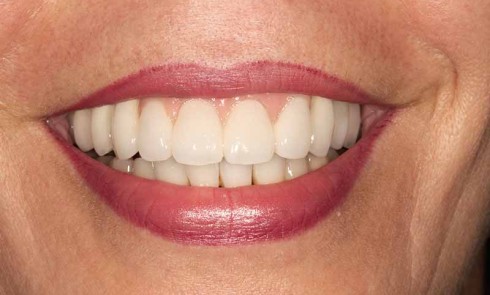

Article réservé à nos abonnés L’infiltration en profondeur – Partie II

D’autres équipes ont confirmé récemment nos premiers résultats [5, 3]. Toutefois, certaines taches n’étaient pas masquées par cette infiltration superficielle,...